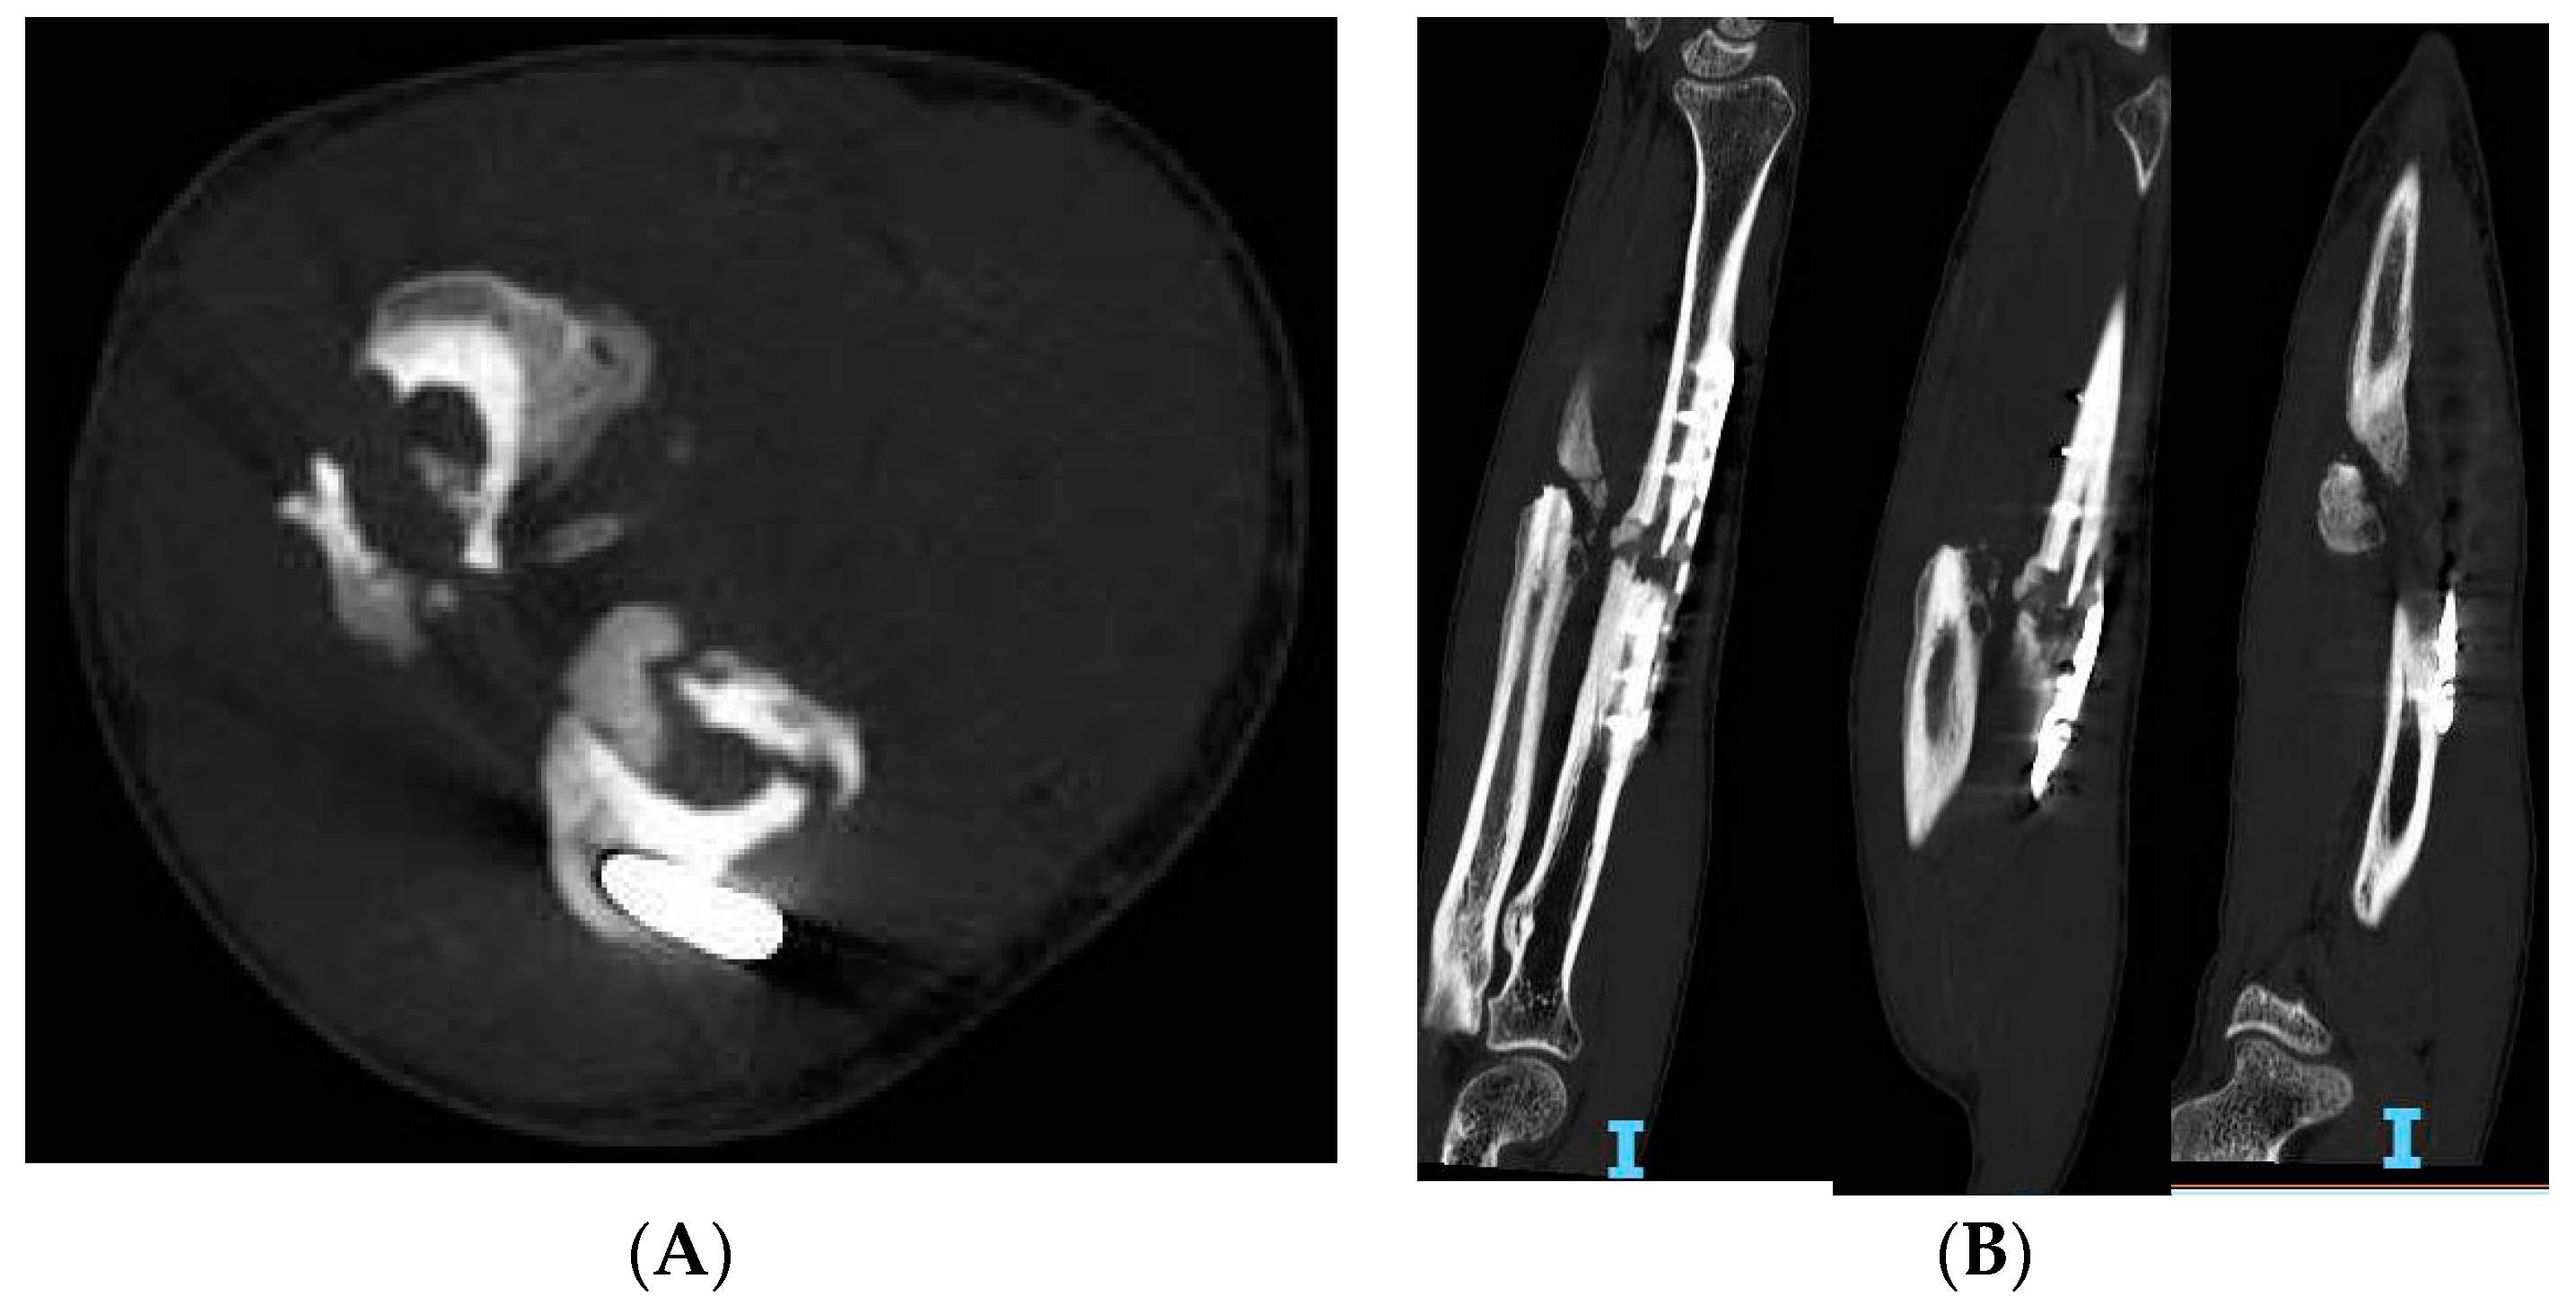

2.1. Risk Factors

2.3. Imaging

2.5. Characterization

4.2. Induced Membrane Technique